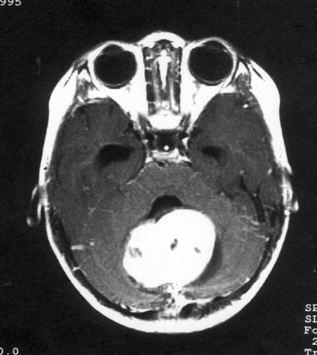

问题 病历摘要:??患儿男性,11岁。半年前开始出现行走不稳,常无故跌倒。半月前出现发作性剧烈头痛,伴恶心呕吐。体检:T36℃,P100次/分,R22次/分,BP100/60mmHg,神清,言语较缓慢,双眼外展约不及边,双眼侧视时有小幅度水平眼震。四肢肌力正常,右上肢肌张力较低,坐位姿势不稳,常不自主摇晃,双上肢指鼻不准,行走蹒跚步态,足距扩大,身前倾。 患儿目前出现了哪些方面的临床症状

选项 A.颅内压增高表现 B.小脑蚓部损害表现 C.动眼神经损害 D.滑车神经损害 E.展神经损害 F.面神经 G.锥体束征 H.锥体外系损害

答案 ABE